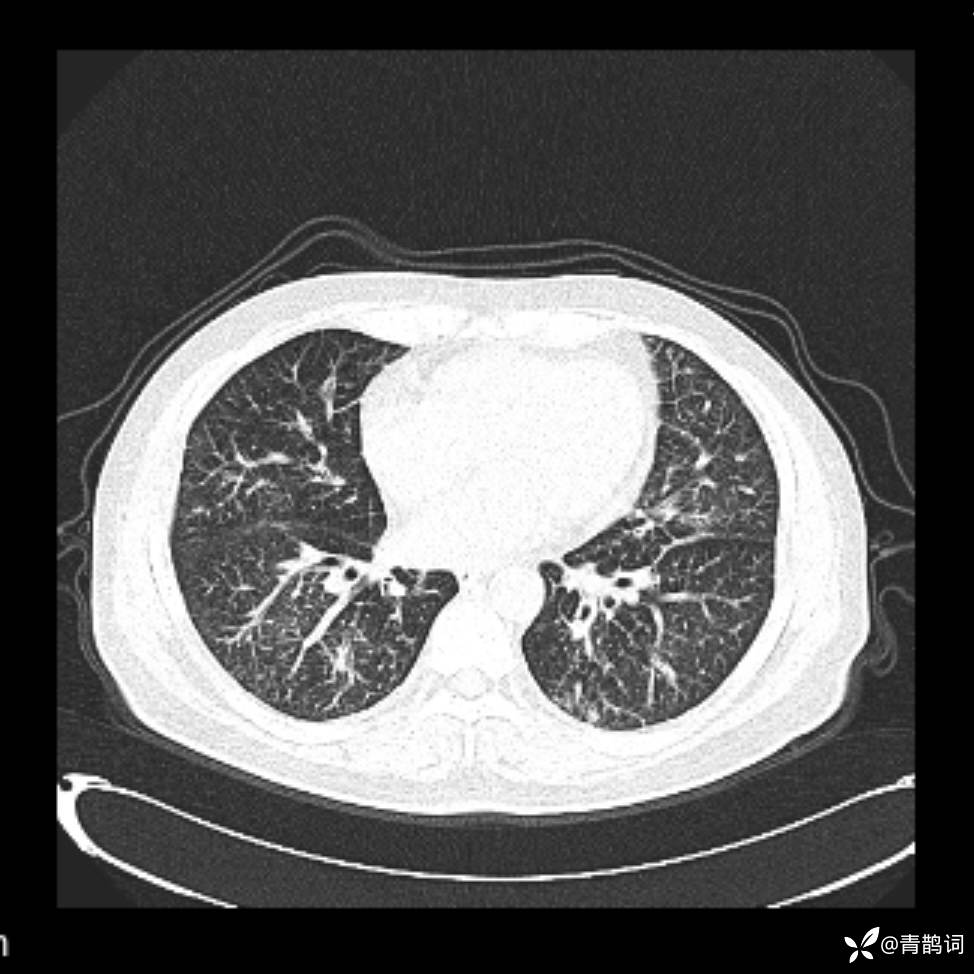

患者年龄:30岁。

患者性别:男。

简要病史:左颜面部肿胀2年,反复咳嗽咳痰,逐渐加重。

结合病史及影像学表现,期待评论区各位老师各抒己见~